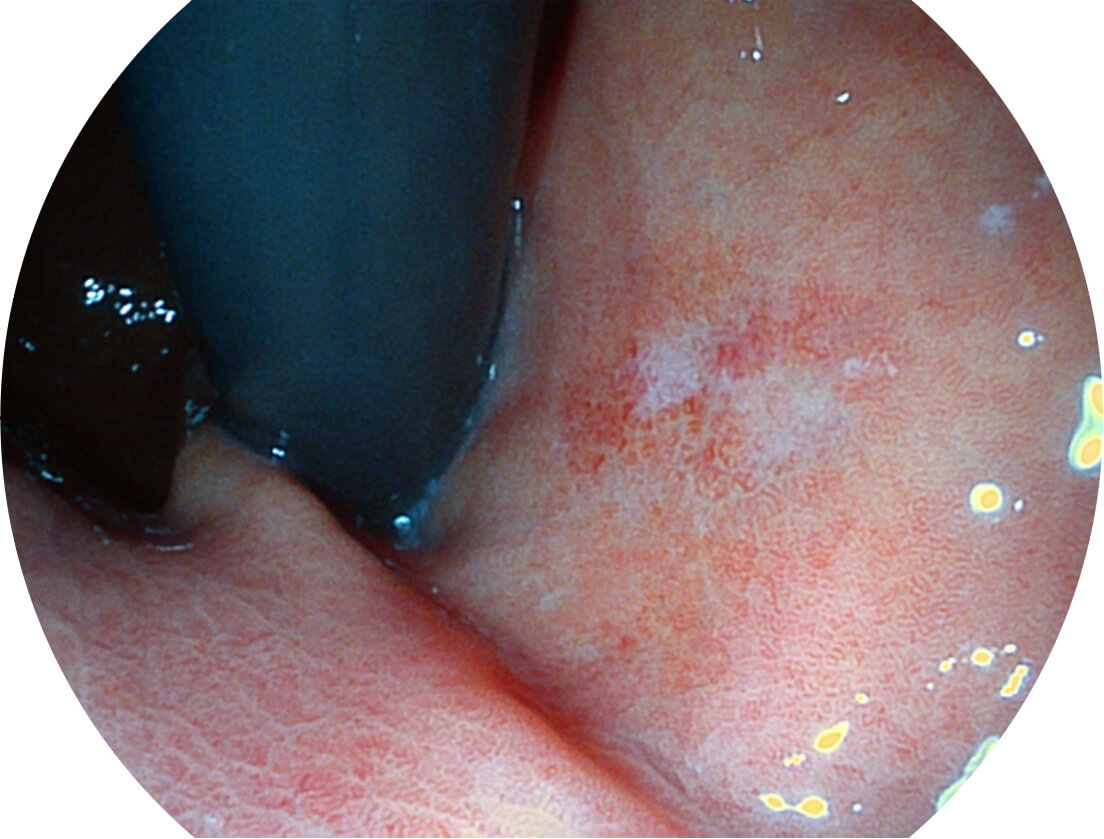

强调浅层黏膜结构的同时,保证照明亮度和提升浅层微血管与中层血管颜色对比度,病变边界更清晰。

• 白光图像 VIST图像